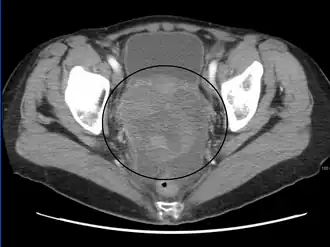

CT scanning is preferred to assess the extent of the tumor in the abdominopelvic cavity, though magnetic resonance imaging can also be used.[28] CT scanning can also be useful for finding omental caking or differentiating fluid from solid tumor in the abdomen, especially in low malignant potential tumors. However, it may not detect smaller tumors. Sometimes, a chest x-ray is used to detect metastases in the chest or pleural effusion. Another test for metastatic disease, though it is infrequently used, is a barium enema, which can show if the rectosigmoid colon is involved in the disease. Positron emission tomography, bone scans, and paracentesis are of limited use; in fact, paracentesis can cause metastases to form at the needle insertion site and may not provide useful results.[29] However, paracentesis can be used in cases where there is no pelvic mass and ascites is still present.[29] A physician suspecting ovarian cancer may also perform mammography or an endometrial biopsy (in the case of abnormal bleeding) to assess the possibility of breast malignancies and endometrial malignancy, respectively. Vaginal ultrasonography is often the first-line imaging study performed when an adnexal mass is found. Several characteristics of an adnexal mass indicate ovarian malignancy; they usually are solid, irregular, multilocular, and/or large; and they typically have papillary features, central vessels, and/or irregular internal septations.[31] However, SCST has no definitive characteristics on radiographic study.[32]

In advanced cancers, where complete removal is not an option, as much tumor as possible is removed in a procedure called debulking surgery. This surgery is not always successful, and is less likely to be successful in women with extensive metastases in the peritoneum, stage- IV disease, cancer in the transverse fissure of the liver, mesentery, or diaphragm, and large areas of ascites. Debulking surgery has usually only been done once[28] but a recent study has shown a longer overall survival in recurrent ovarian cancer when surgery combined with chemotherapy was performed compared to treatment with chemotherapy alone.[100] Computed tomography (abdominal CT) is often used to assess if primary debulking surgery is possible, but low certainty evidence also suggests fluorodeoxyglucose‐18 (FDG) PET/CT and MRI may be useful as an addition for assessing macroscopic incomplete debulking.[101] More complete debulking is associated with better outcomes: women with no macroscopic evidence of disease after debulking have a median survival of 39 months, as opposed to 17 months with less complete surgery.[26] By removing metastases, many cells that are resistant to chemotherapy are removed, and any clumps of cells that have died are also removed. This allows chemotherapy to better reach the remaining cancer cells, which are more likely to be fast-growing and therefore chemosensitive.[29]